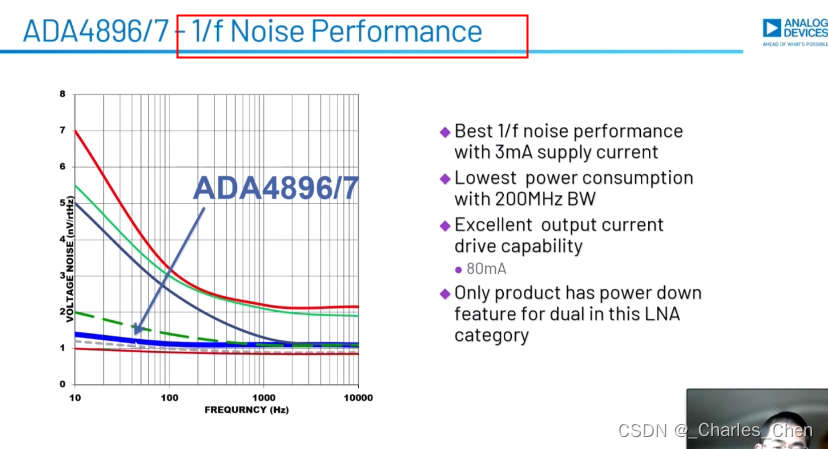

低噪声放大器(LNA)

接收机中的LNA必须具有出色的噪声性能和足够增益。对于设计合理的接收机,LNA将决定整个接收机的噪声性能。传感器单元通过较长的同轴电缆连接到相应的低阻抗LNA的输入端。如果没有适当的电缆终端匹配,电缆电容和传感器单元的源阻抗将大大制约从宽带传感器接收信号的带宽。传感器电缆匹配至低阻,有助于降低这一滤波的影响,有效提高图像质量。不幸的是,这种端接也降低了LNA的输入信号,因而降低接收灵敏度。由此可见,为LNA提供有源输入端接非常重要,可以在上述条件下提供必要的低输入阻抗端接和出色的噪声性能。

CWD接收机通常使用两种方法处理CWD信号。第一种方法是高性能超声系统在LNA输出端提取接收到的CWD信号。本振频率等于发送频率的混频器对信号进行波束成形,再混频至基带进行处理。I/Q本振信号可以逐通道调整相位,对接收到的CWD信号相位进行偏移。混频器输出相叠加,经带通滤波器,最后进入ADC进行采样。采样得到的基带波束信号处于音频范围(100Hz至50kHz),采用工作在音频频率范围的ADC对I和Q CWD信号进行数字化。这些ADC需要出色的动态范围,以便处理运动组织产生的较大的低频多普勒信号和血液产生的微弱信号。